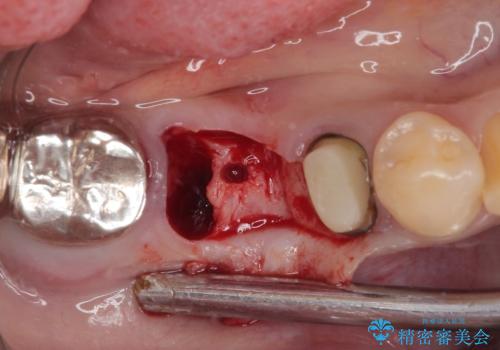

左下小臼歯は根管治療で対応する予定でしたが、診断のために歯肉を開いたところ頬側に垂直破折が認められたため、抜歯即時埋入インプラントによる補綴治療を選択することとしました。